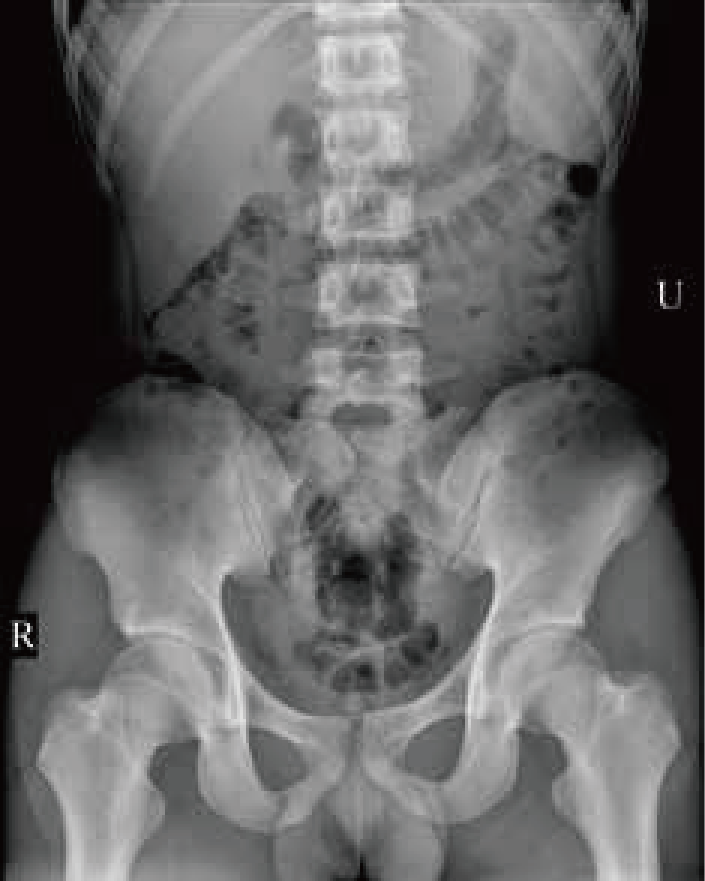

臨 床 圖 集